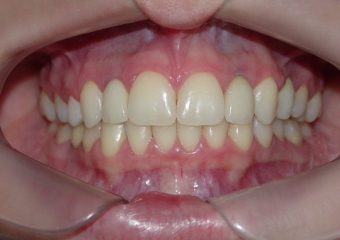

Próteses de porcelana sobre implantes

Sorriso final do caso terminado em maio de 2012